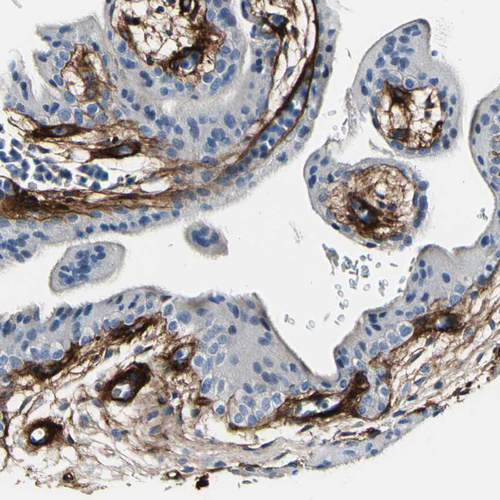

Immunohistochemical staining of human ovary shows moderate cytoplasmic positivity in connective tissues.